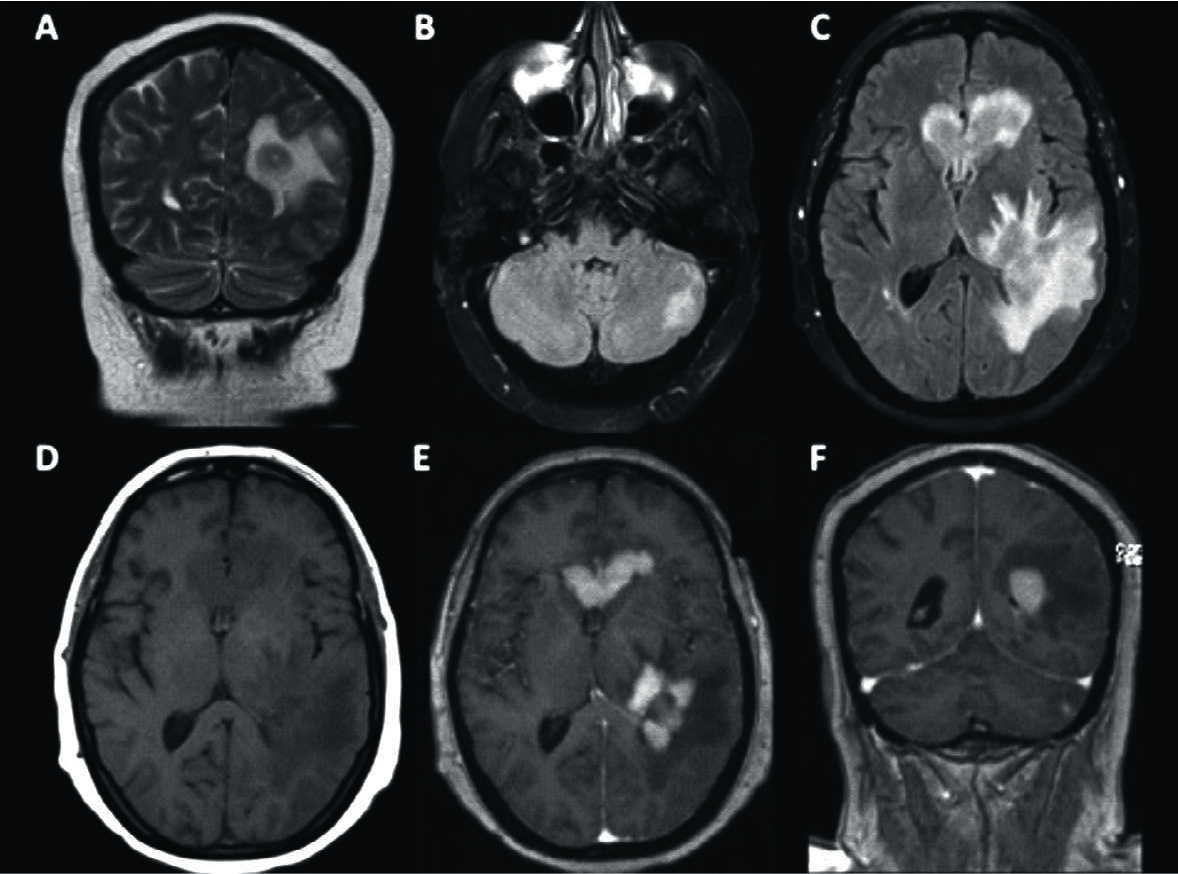

Figura 3

LPSN con compromiso multifocal supra e infra-tentorial.

Paciente de 53 años con cefaleas progresivas y diagnóstico de LPSN multifocal. Se identifican focos supra-tentoriales hipointensos en T2 (A) con importante edema asociado en FLAIR y una lesión de fosa posterior (B y C). En T1 son lesiones de baja señal (D) presentando con gadolinio un intenso realce y con bordes irregulares (E y F). A nivel infra-tentorial la lesión es cerebelosa izquierda (B y F).